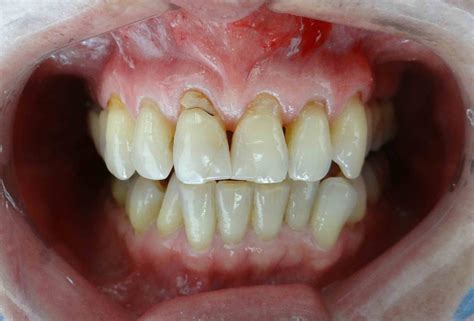

La retracción de las encías es una enfermedad periodontal en la que el tejido gingival que rodea al diente se desliza hacia arriba, dejando expuesta la raíz del diente. Puede ocurrir en uno o en varios dientes a la vez. Al retraerse el tejido, las encías lucen separadas de los dientes y se pueden formar bolsas en las que se acumula placa dental. Además, las piezas dentales lucen más alargadas, lo que afecta la sonrisa del paciente.

Si notas que tus dientes parecen más largos de lo normal, es probable que estés ante unas encías retraídas. Esta es una de las señales más claras y pueden provocar una desproporción en la sonrisa. La línea de las encías aparece más arriba de lo que debería estar y genera un cambio estético importante, capaz de afectar la autoestima de las personas. Las encías quedan expuestas, los dientes tienden a cambiar de color y, en general, altera el aspecto de la sonrisa.